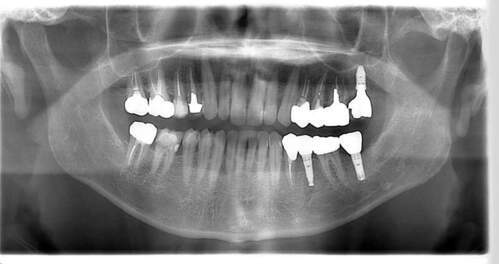

インプラント治療の症例4

レントゲン写真

- Befor

- After

口腔内写真

| 年齢 | 50代・男性 |

|---|---|

| 主訴 | 部位:左下6番7番 主訴:左下奥歯腫れて痛い。 |

| 治療内容 | 左下6番抜歯、左下6番7番骨造成、インプラント埋入 |

| 治療費 | 合計:1,232,000円 ・内訳 診断料:55,000円 サージカルガイド2本:66,000円 GBR:110,000円×2本 埋入料:165,000円×2本 静脈内鎮静麻酔:77,000円 2次OPE:22,000円×2本 仮歯:55,000円×2本 上部構造(フルジルコニア):165,000円×2本 (2023年1月現在) |

| 治療期間 | 約8ヶ月 |

| リスク・副作用 | リスク・副作用 |

| 治療方針 | 元々支台歯に負荷がかかりやすいとされている延長ブリッジを抜歯し、1本単体でしっかりかめるようにインプラントを2本埋入した。骨吸収も進んでいたため、※GBR法で骨造成を同時に行った。 治療と並行して、全顎的な歯周病治療も行い、今後は歯周病が進行しないよう、こまめにメンテナンスに通っていただく。 |

| 特記事項 | ※1 GBR・・・骨再生誘導法。骨の高さや厚みを人工骨や人工膜などを使用し再生する方法 |

| 担当者所見 | 6番は歯根分割された被せ物が7番の欠損部との延長ブリッジとされており、強い咬合と歯周病も相まって負荷がかかり動揺し、歯として機能しなくなったため、抜歯となった。 |